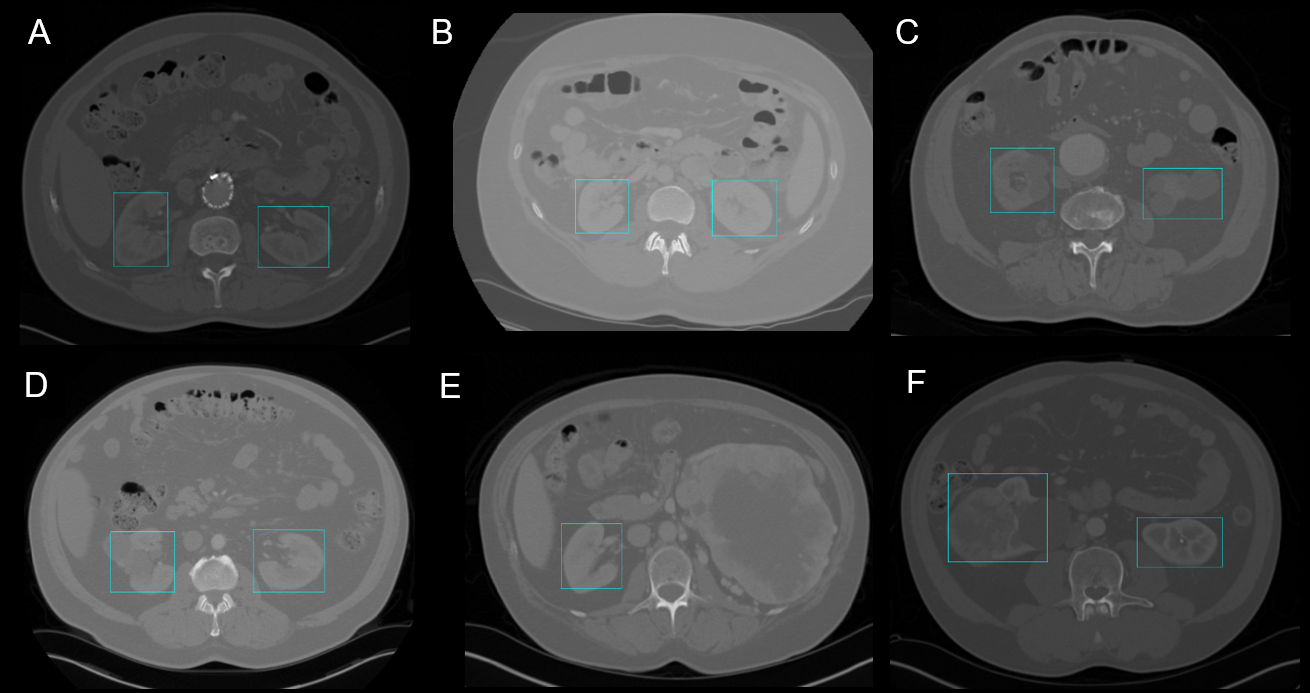

Organ detection is useful for various medical applications, whether it is to plan surgeries or to find pathologies. Adding bounding boxes to organs can also be the first step before applying other image processing methods like segmentation [2], [4]. Real-time organ tracking can be profitable for adaptive radiotherapy [5] or laparoscopic surgeries [3]. Object detection models could help with these tasks. This article focuses on 2D and 3D kidney detection. Recognition of kidneys can be challenging considering the variety of forms, textures, positionings and contrasts found in CT scans (Figure 1).

YOLO showed high detection scores for the training and test sets in 2D (Dice score > 0.85) as seen in Table 1. Cystic, cancerous and healthy kidneys were recognized and located properly in CT scans largely varying in contrasts and intensities (Figure 1). The presence of artifacts caused by metal stents did not affect the performance of the model.

Difficulty with unknown ratios. The drop in performance from the training to the test set is mainly due to the failed recognition of kidney morphology unknown to the model. For instance, in Figure 1E, the kidney presented on the right has an unusual size and shape. The model only recognizes and locates the other kidney. In fact, it is known that YOLO struggles to generalize to new or unknown ratio configurations [8]. The model did well on regular looking kidneys even with tumors or cysts (Figure 1C, 1D and 1F) as long as the general morphology is preserved.

Coarseness of bounding boxes. Another factor affecting the scores is the coarseness of the boxes generated. When an object is localized, the box might not be properly framed or fitted (Figure 1F). It is reported that YOLOv3 struggles with perfectly aligning boxes with the detected objects [7].